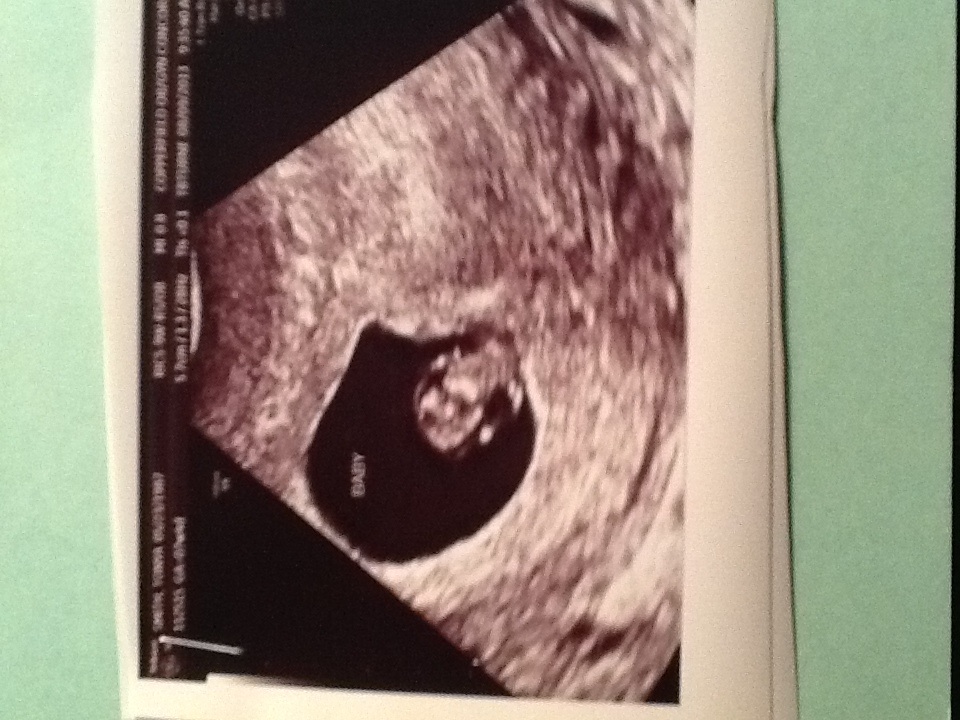

I had my very first appt this morning ! I was right where I thought I was 7 weeks 5 days ! I have a healthy bean right where it's supposed to be ! I'm staying with a due date of March 24 ! My bean had a strong heart beat of 156 !! God is good to bless DH and I with this precious gift !!